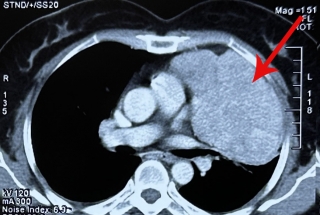

Tại Bệnh viện Ung Bướu Hà Nội, kết quả chụp cộng hưởng từ cho thấy, khối u của bệnh nhân bị hoại tử phần trung tâm, tổn thương xâm lấn cơ cắn, chèn ép cơ ức đòn chũm trái, đè đẩy bó mạch cảnh cùng bên, ngoài ra còn có một số hạch rải rác vùng cổ trái. Khối u đã xâm nhiễm ra da gây hoại tử chảy máu, chảy dịch liên tục. Bệnh nhân lại có bệnh bụi phổi cũ nên tâm lý khá lo lắng đến tính mạng.

Trước ca phẫu thuật, TS.BS. Đàm Trọng Nghĩa, Trưởng khoa Ngoại Đầu cổ cho biết, sau khi giải phẫu bệnh mới có thể xác định khối u là lành tính hay đã ác tính hóa nhưng việc để phát triển đến kích thước lớn như vậy sẽ dính vào các tổ chức lân cận, cùng việc bệnh nhân đã cao tuổi khiến cuộc mổ đối mặt với nhiều nguy cơ tai biến như chảy máu, liệt thần kinh mặt. Trước mổ các bác sĩ phải dự trù sẵn máu truyền cho bệnh nhân, làm đầy đủ các xét nghiệm cần thiết cho cuộc mổ như chụp Cộng hưởng từ, đo chức năng hô hấp…, đồng thời giải thích động viên cho bệnh nhân yên tâm điều trị.